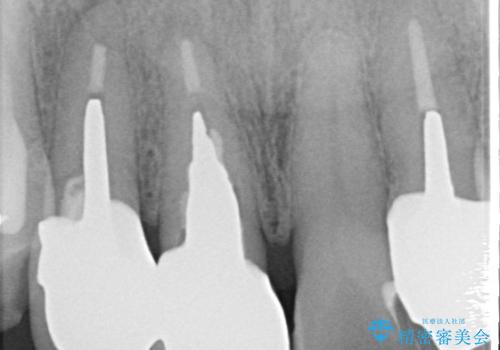

古い被せ物を除去しオールセラミッククラウンで治療を行いました。

被せ物の適合が悪く劣化もおこし色が変色している状態でした。そのため他の歯とも色が合っていませんでした。古い被せ物を除去し形を整えた後にオールセラミッククラウンで治療を行いました。